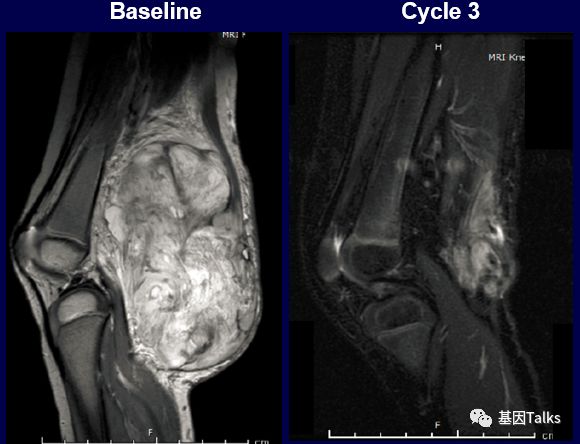

(2)1例婴儿纤维肉瘤合并ETV6-NTRK3融合:

(3)1例分泌性乳腺癌合并ETV6-NTRK3融合: